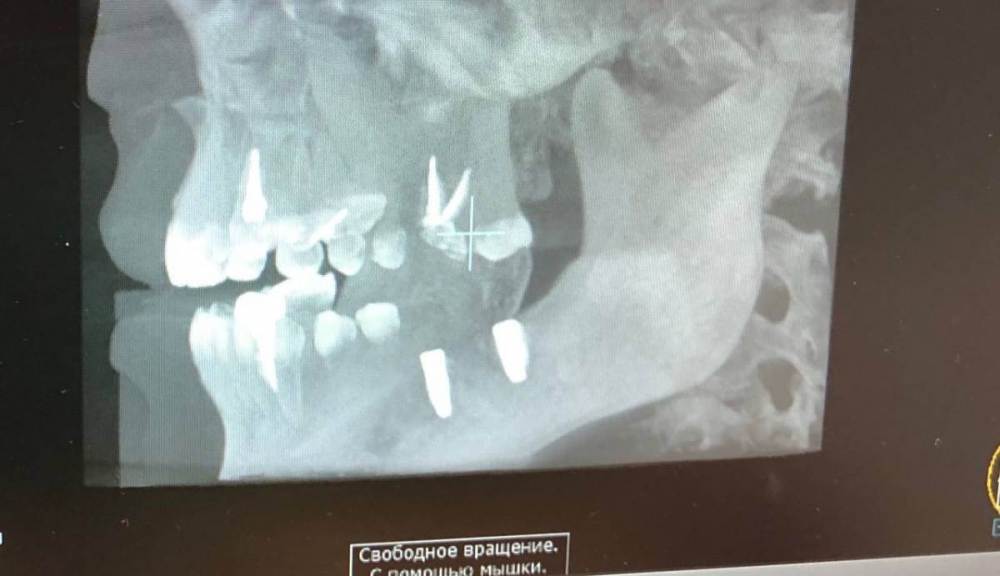

Здравствуйте ! Ситуация следующая - 6 сверху коронка с резекцией , долгое время осталась без антагониста , соотвественно выдвинулась (это уже мое предположение) . Чтобы спасти зуб , доктор принял решение повести гемисекцию корня . После - осталась рассечена десна .. Доктор говорит десна заживет , но визуал мягко говоря напрягает , так как при улыбке у меня это все видно ..

Фото 7,8 - Также была проведена резекция кисты 5 зуба снизу , с коронкой , и установка 7 импланта в качестве антагониста верхней 7 . Одной операцией . Коронка оголилась , швы сняли на 3 день .. доктор также утверждает что в дальнейшем будет все хорошо , зарастет . Также очень смешает внешний вид десны , десна стала волной даже на 6 ..